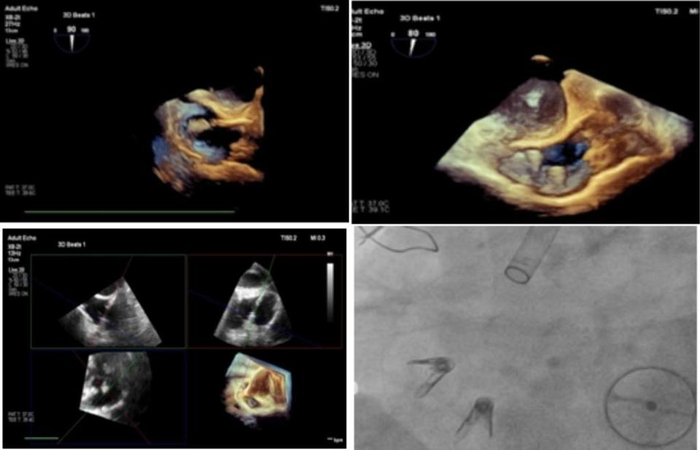

患者老年女性,因“双下肢水肿,伴活动后四肢乏力半年”入院。既往二尖瓣置换术20多年,高血压病史20年、糖尿病史4年。心脏超声检查示:三尖瓣重度反流。入院诊断有心脏瓣膜病、三尖瓣关闭不全(重度)、主动脉瓣关闭不全(中度)、肺动脉高压(中度)、二尖瓣置换术后 心功能IV级(NYHA分级)、高血压(2级,很高危)、2型糖尿病 、心律失常、持续性房颤。 STS评分示外科手术高危。经食道超声提示:右心房扩大,瓣环扩张,瓣叶拴系高度6mm,隔叶栓系引起前叶、后叶与隔叶间错位,后隔间隙最宽约8.8mm,反流缩流颈宽度12.7mm,反流量68ml,右房面积21.7cm2,TAPSE:23mm。

该患者二尖瓣机械瓣置换术后,隔瓣受牵拉导致瓣叶拴系,对和不良,三个瓣叶相互之间GAP较大。经团队综合评估,决定在三尖瓣后隔瓣环交界处植入12T K-Clip®、前后瓣环交界处植入14T K-Clip®,通过缩小瓣环、增加瓣叶对合,达到关闭缝隙、改善反流的效果。

患者全麻后,行右侧颈静脉穿刺,将12T K-Clip®系统送达右心房内。在经食道超声引导下,对K-Clip®系统进行调姿,指向目标瓣环区,将K-Clip®锚定到位,打开夹持臂到最大角度,夹合,评估反流改善情况,解离器械退出系统。同样方法将14T K-Clip®系统夹合于前后瓣交界处。超声评估示反流下降至轻—中度,冠脉造影示冠脉血流与术前相同,达到满意效果,缝合血管,手术结束。患者术前重度三尖瓣反流。术前三尖瓣环面积10.3cm²,周长11.5cm;术后三尖瓣环面积6.6cm²,周长9.3cm。